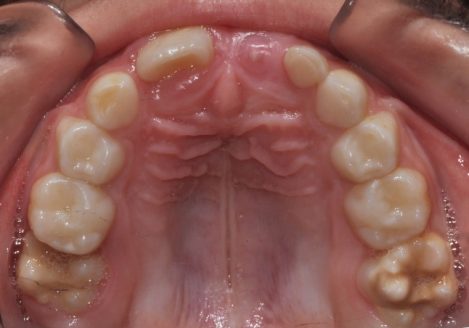

Ортодонтско лечение при множествена хиподонтия. Клиничен случай.

Статията обсъжда клиничните аспекти на проблема – множествена хиподонтия. Решението и планът на лечение при тези пациенти включват дългосрочни цели и съобразяване с костното развитие на пациента както до завършване на растежа му, така и при неговото остаряване. Често лечението на тези клинични случай завършват с протетичното им възстановяване. Затова ортодонтското лечение трябва да е съобразено с крайното дефинитивно възстановяване на съзабието.